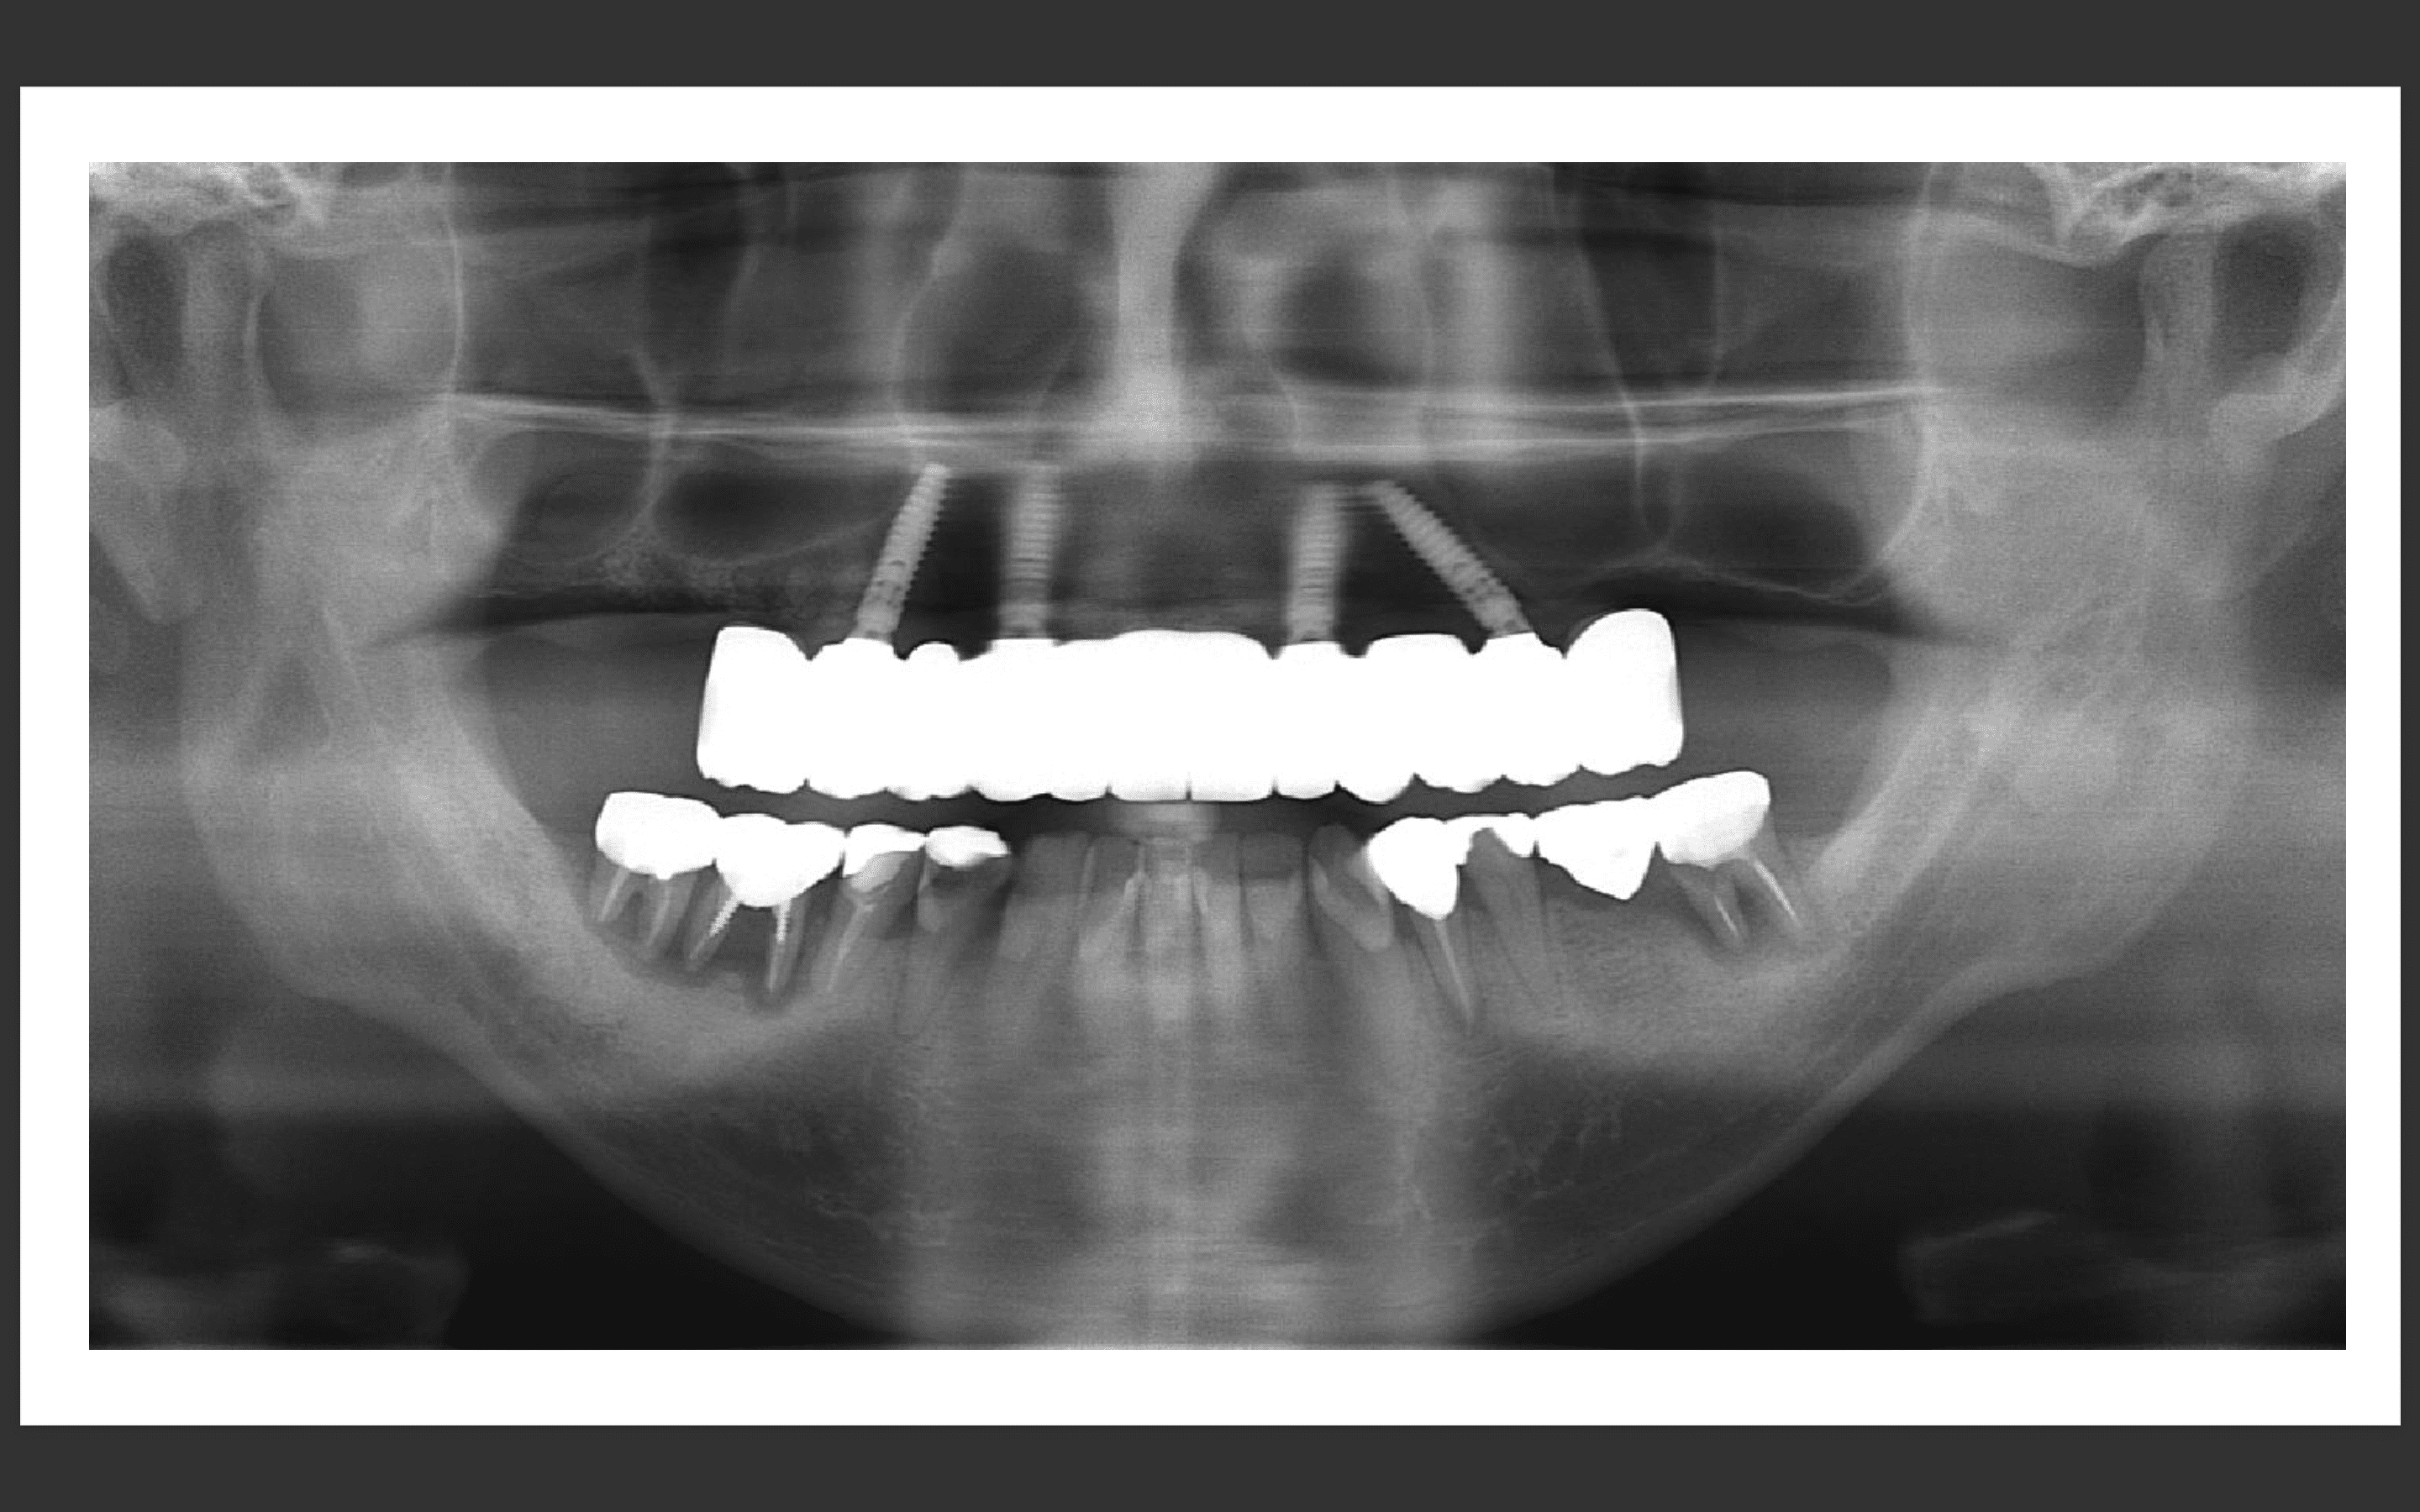

パノラマX線

上顎:根の病気と虫歯で保存不可のな状態。

下顎:インプラントが不適切な位置に入っており、撤去が必要な状態。